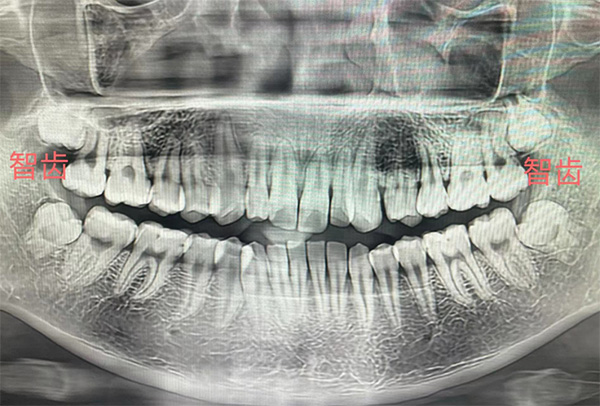

智齿是我们俗称的“尽头牙”,是指人类口腔内牙槽骨上最里面的第三颗磨牙,上下颌各2颗。由于它萌出时间很晚,一般在17~25岁间萌出,此时人的生理、心理发育都接近成熟,有“智慧到来”的象征,因此被俗称为“智齿”。

智齿是最容易引发问题的牙齿。智齿在萌出过程中或萌出困难时,牙冠的一部分被游离的牙龈组织所覆盖,在牙冠与龈瓣之间形成盲袋,盲袋内经常有食物残渣和细菌存留。这种局部条件使细菌容易生长、繁殖,可诱发智齿冠周炎。因智齿萌出时常缺乏足够位置而易形成阻生,故本病多见于该牙。临床上常见的阻生情况有近中阻生、水平阻生和垂直阻生等。